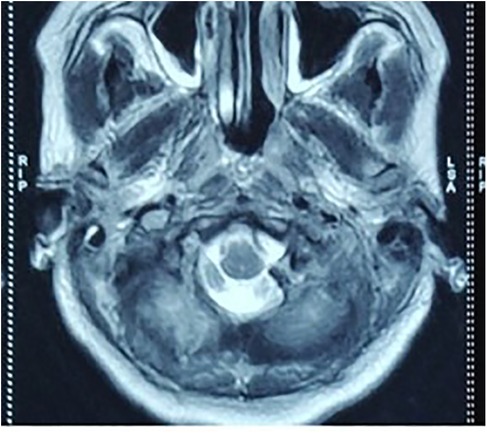

A 26-year-old woman presented to the emergency department following an RTA. At presentation, the Glasgow Coma Score (GCS) of the patient was E4V5M6, but she was clinically drowsy and easily roused with a normal bilateral pupillary response. She had no associated injury. On examination, the patient had normal motor and sensory responses in all four limbs. Local examination revealed contusions over the left mastoid region and the left lateral aspect of the neck. An non-contrast computed tomography (NCCT) brain scan was performed, which was suggestive of a fracture of the left occipital condyle with a lacerated fragment in the foramen magnum extending into the jugular foramen (Figures 1a–c). The right occipital bone was also fractured. The patient began to experience difficulty swallowing, accompanied by regurgitation of liquid from the nose. She showed signs of IX and X cranial nerve palsy. On examination, she also had left winging of the scapula, indicating XI cranial nerve palsy. MRI was advised, which showed mild pre-vertebral soft tissue thickening with no compression over any neural structure by a dislocated fragment or any ligament instability (Figure 2). She was managed conservatively and fitted with a hard cervical collar, and she remained hospitalized for 7 days. Over the 7 days, she was fed via a nasogastric tube, which was removed as her swallowing function improved. Gradually, her symptoms improved. At a follow-up examination 3 months after the injury, she had achieved complete recovery with minimal residual neck pain.

CT scan images and illustrations of a skull. (a) Axial view showing bone structures. (b) Coronal views displaying multiple sections of the skull. (c) Three-dimensional reconstruction highlighting bone fractures. (d) Diagram noting fractures in the occipital region, with annotations explaining the injuries.

Figure 1. Axial (a) and coronal (b) section NCCT scan of the first patient with virtual reconstruction (c) and pictorial diagram (d) of the fracture (axial craniocaudal view).